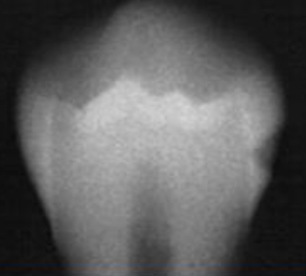

- Difficult to detect on radiographs due to small width of lesion and density of superimposing enamel - (occlusal caries)

Incipient occlusal caries

- Broad-based thin radiolucent zone in dentin with no changes in enamel - Noticed as a relative increase in opacity between pulp and caries - (occlusal caries)

Moderate Occlusal caries